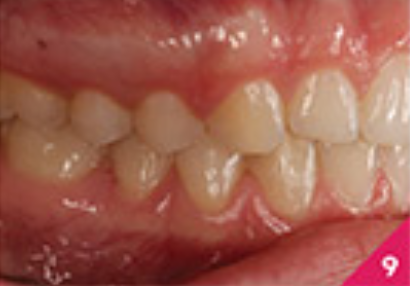

Лікування показало хороші результати, які можна побачити на фото з 6 по 10. Лікар відмітила, що протягом процесу лікування з'явилася незначна рецесія ясен на правому центральному різці нижньої щелепи. Пацієнтку було скеровано на консультацію до пародонтолога та, можливо, трансплантацію ясен.